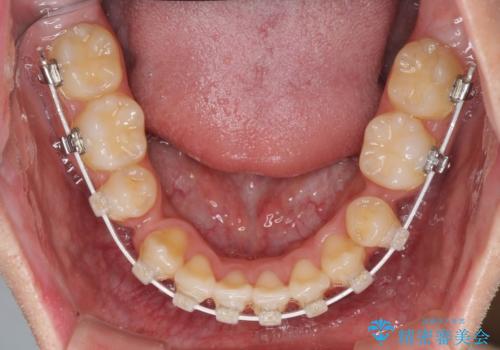

- 矯正装置

- 審美装置

- 上下の八重歯や乱杭歯を気にして来院され患者様です。

スペースを確保するため、上下左右の小臼歯を抜歯し、ワイヤー装置に矯正することとしました。

奥歯の咬み合わせの左右差が大きかったため、変則的な抜歯矯正を行いました。

治療期間はやや長期化しましたが、満足のいく歯並びとなりました。